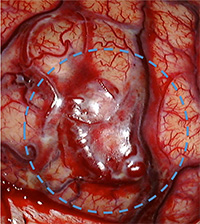

脳動静脈奇形に関与する動脈、静脈、奇形部分本体を周囲の脳組織から剥離して、摘出します。脳動静脈奇形の大きさ、場所によって手術の難しさは異なりますが、正常な血管と、異常な血管を見分けながら、奇形部分のみを取り出す必要があり、脳神経外科手術の中でも難しく、そして時間のかかる手術の一つです。

脳出血による半身麻痺と意識障害で発症した患者さまの治療前後の血管撮影を下に示します。(赤線内が脳動静脈奇形の部分)

手術中の血管奇形部分の写真。青丸部分に拡張した血管網が見られます。(下図)

(画像は、日本赤十字社医療センター 脳神経外科 野村竜太郎先生のご好意による)